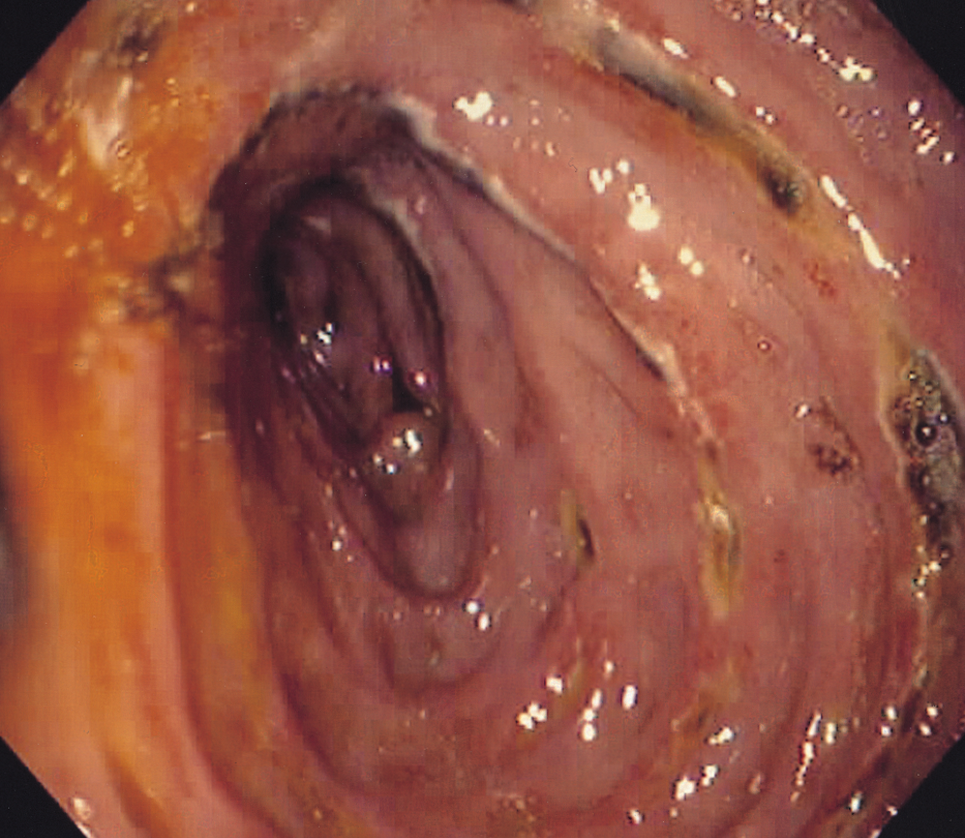

اختبارات المسح (الأشعة المقطعي، التصوير بالرنين المغناطيسي، والموجات فوق الصوتية بالمنظار). يهدف هذا الفحص إلى رؤية صورة العضو والبحث عن مكان الورم. - التنظير الهضمي العلوي. إنه فحص إضافي حيث سيتم تخدير المريض محليًا قبل إجراء هذا الإجراء.